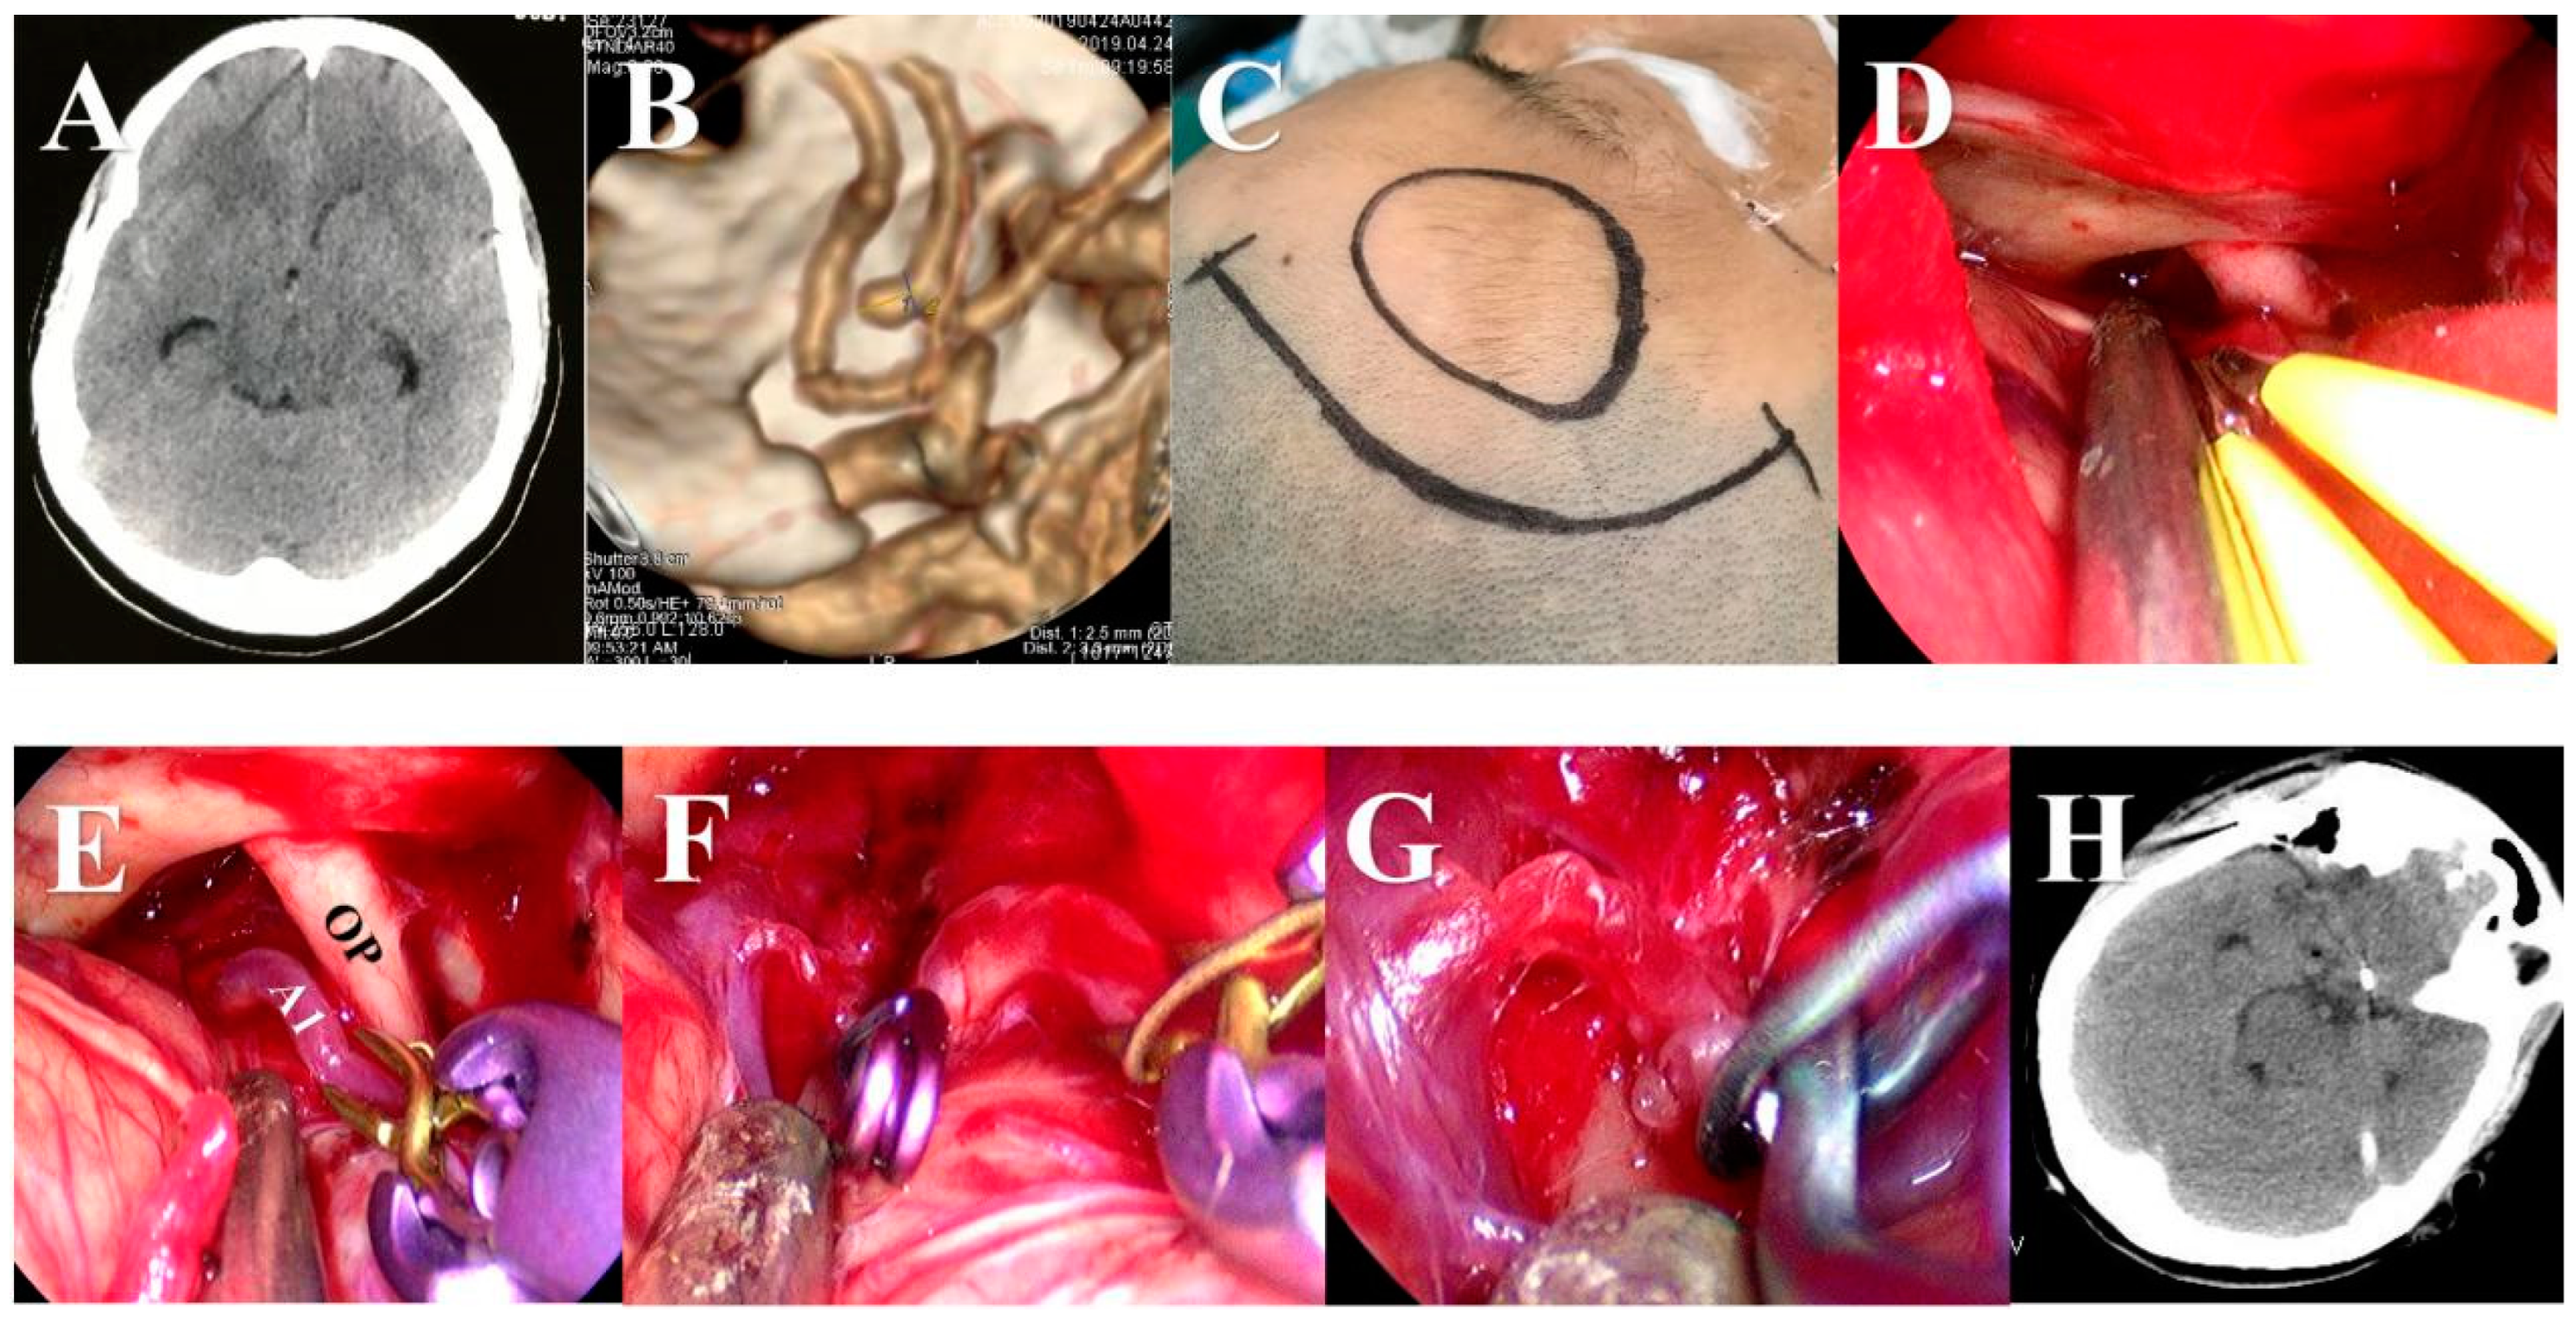

Surgical Clipping of Intracranial Aneurysms Using a Transcranial Neuroendoscopic Approach

2.3. Surgical Procedures